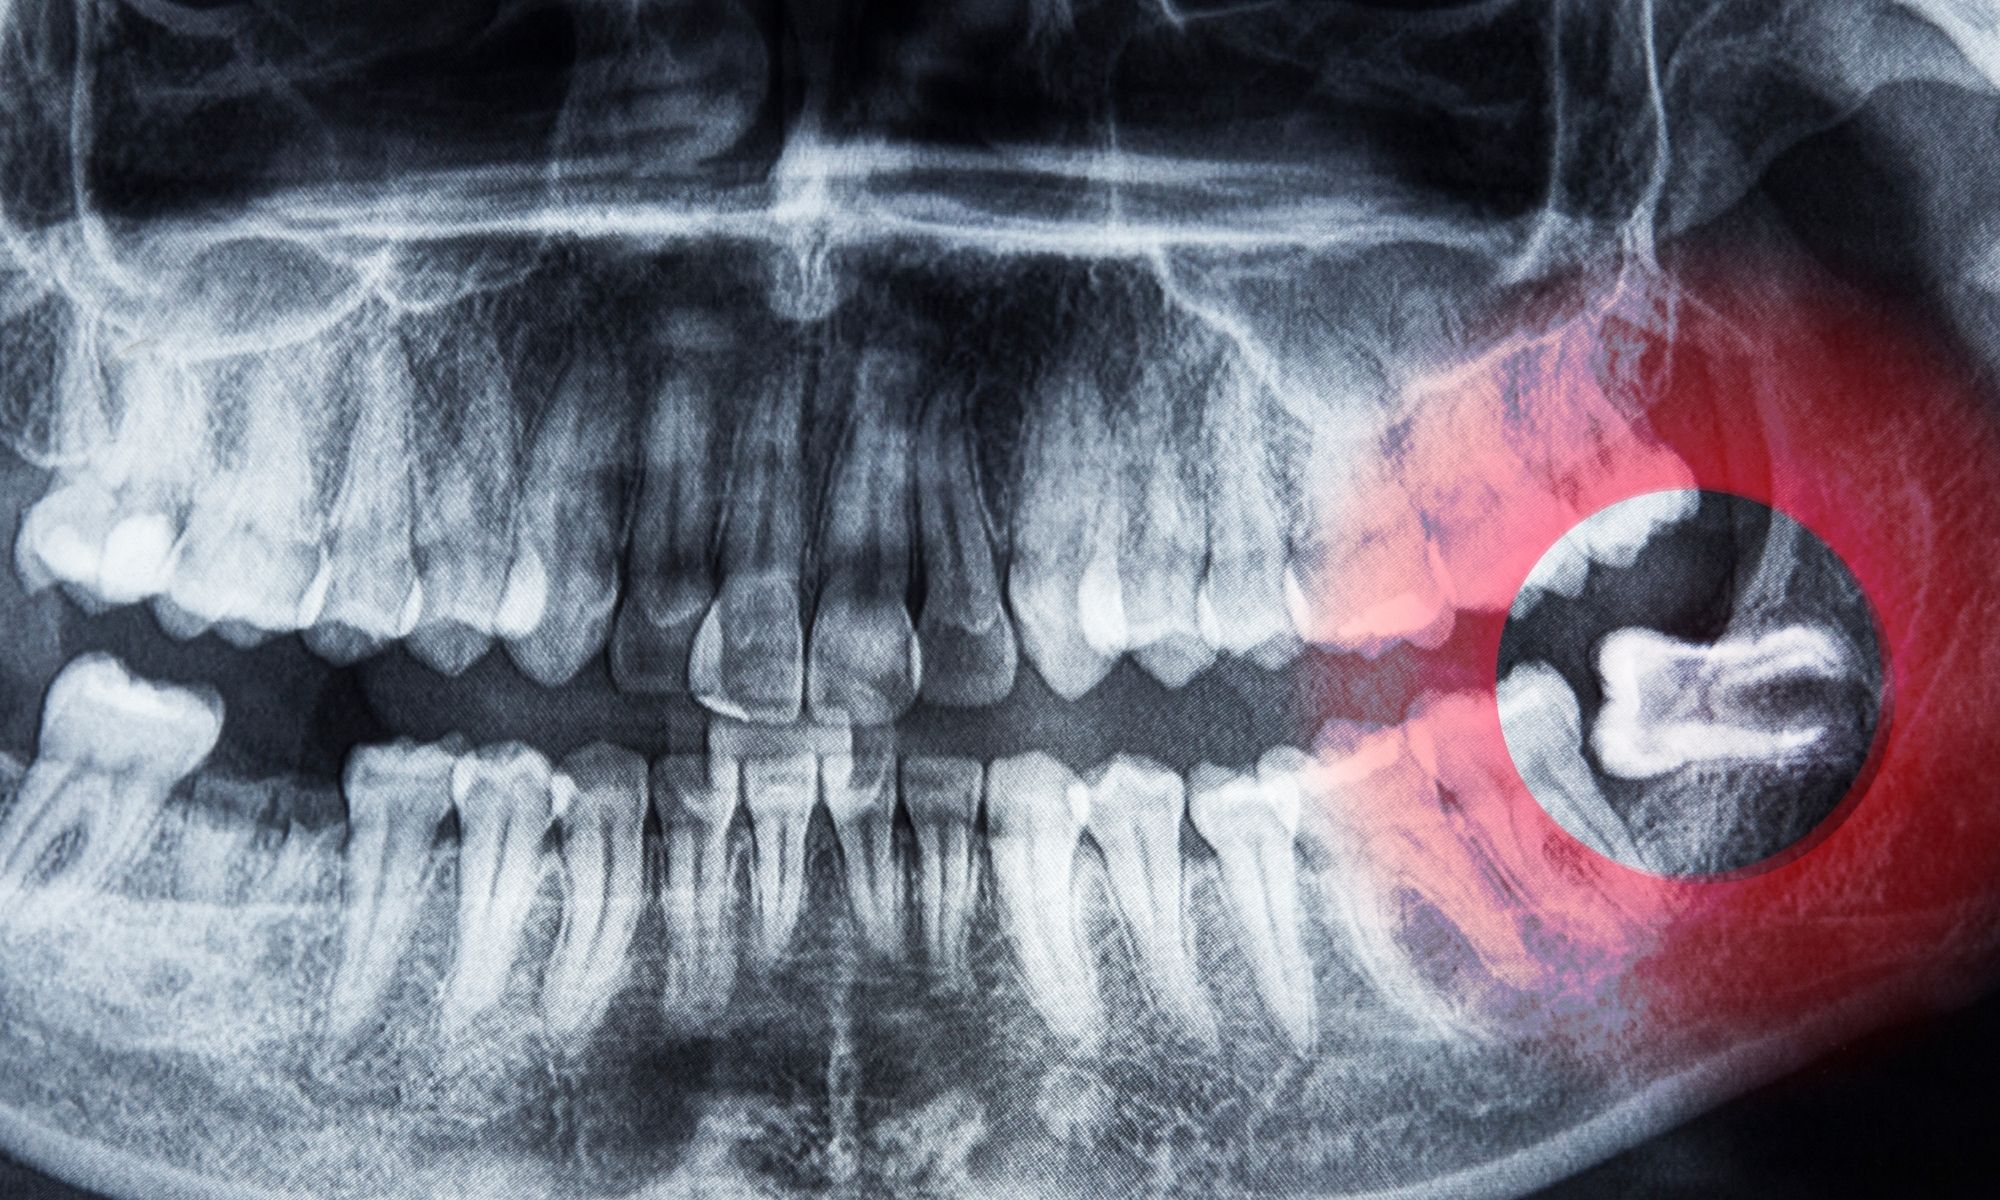

Chảy máu sau nhổ răng là hiện tượng khá phổ biến, đặc biệt khi nhổ răng khôn hoặc răng có chân sâu. Thông thường, tình trạng này kéo dài khoảng 30 phút đến vài giờ và sẽ tự ngưng khi cục máu đông hình thành ổn định trong hố răng. Tuy nhiên, nếu máu vẫn tiếp tục chảy rỉ rả sau 24 giờ, gạc ướt đẫm hoặc máu đỏ tươi ra nhiều trong khoang miệng, đó là dấu hiệu bất thường cần được xử lý đúng cách.

Nguyên nhân khiến vết nhổ răng tiếp tục chảy máu thường do cục máu đông bị bong ra sớm vì người bệnh súc miệng mạnh, khạc nhổ, hút thuốc hoặc uống nước bằng ống hút. Cồn và lực hút có thể khiến mạch máu co giãn thất thường, làm vết thương khó liền. Ngoài ra, những người đang sử dụng thuốc chống đông, bị cao huyết áp, rối loạn đông máu hoặc viêm nhiễm nướu cũng có nguy cơ chảy máu kéo dài hơn bình thường.

Nếu đã làm đúng hướng dẫn mà máu vẫn chảy liên tục, kèm đau tăng, sưng to hoặc có mùi hôi, rất có thể có mạch máu bị tổn thương, ổ răng viêm hoặc sót chân răng. Khi đó, người bệnh cần đến ngay nha sĩ hoặc bệnh viện răng hàm mặt để kiểm tra, khâu lại vết thương hoặc dùng thuốc cầm máu đặc hiệu.